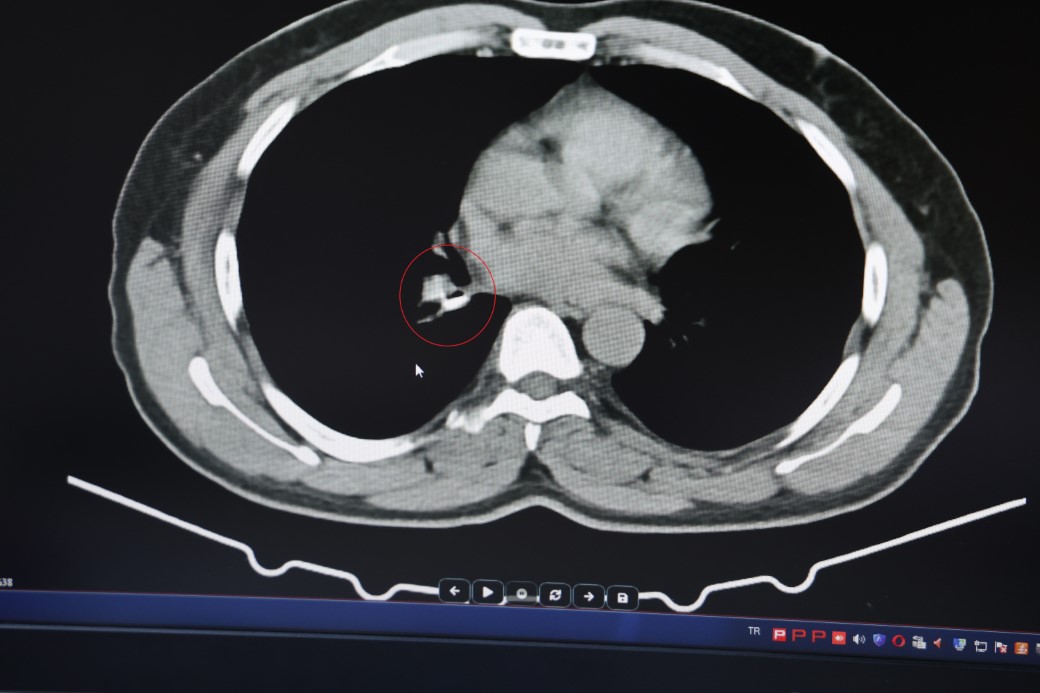

1,5 yıldır astım tanısından sonra tedaviler almaya başlayan İ.U., Prof. Dr. Abdurrahman Şenyiğit’in yanına geldiğinde yapılan tetkiklerde gerçek bambaşka çıktı. Yapılan tomografi ve bronskokopi işlemlerinde akciğere yerleşen maddenin yutulan silikon olduğu belirlendi. Silikonun çıkartılmasıyla hastanın tarifine göre şikayetlerinin ortadan kalktığı belirtildi.

Şenyiğit, o maddenin zamanla akciğer yapısının özelliğini aldığını ve orada yabancı bir madde olarak kaldığına değinerek, "Hastamıza maalesef 2 yıldan beri astım tanısı konulmuş ve sürekli tedavi verilmiştir. Hasta bize geldiği zaman yapılan tomografide sağ akciğer ana bronşun distalinde şüpheli lezyon gördük. Uyguladığımız bronskokopide yabancı maddenin silikon olduğunu tespit ettik. Onu çıkardıktan sonra da hastada bir rahatlama meydana geldi" dedi.